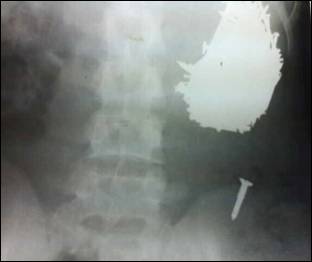

Figure 1: X-ray showing metal objects in the hugely distended stomach.